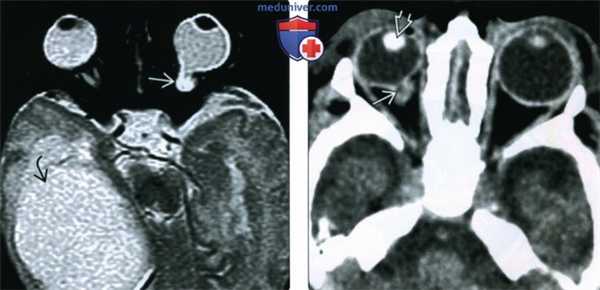

(Слева) При офтальмоскопии видна крупная задняя колобома, в центре которой лежит головка зрительного нерва. Сопутствующая краевая пигментация указывает на вовлечение сетчатки и сосудистой оболочки.

(Справа) При офтальмоскопии визуализируется увеличенный в размерах воронкообразный диск зрительного нерва, содержащий пучок глиальной ткани и окруженный кольцом пигмента; такая картина напоминает цветок вьюнка пурпурного.

• Офтальмоскопия:

о КДЗН: крупный диск с экскавацией; может напоминать глаукоматозную экскавацию о ХРК:

- Белого цвета с пигментированными краями

- Простирается книзу от диска или локализуется снизу

о Аномалия типа «утреннего сияния»:

- Крупный диск зрительного нерва с большой экскавацией; в центре лежит пучок ткани

- Центральный пучок ткани окружен кольцом пигмента; напоминает цветок вьюнка пурпурного

о Перипапиллярная стафилома:

- Центральный кратер, в котором лежит диск зрительного нерва

- Утопленный диск зрительного нерва в остальном не изменен; атрофия окружающего пигментного эпителия